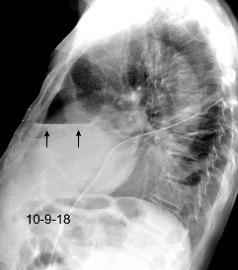

Derrame pleural 43-48% de pacientes con embolismo.

< 1/3 de hemitórax: 90%.(puede haber en lado opuesto).

Siempre exudados.

75% de los pacientes con TEP y derrame pleural tienen dolor pleurítico.

La disnea desproporcionada

Tromboembolismo pulmonar.

Frecuencia del derrame:

Rx: 32%. TC: 47%

Unilateral. 85%

< 1/3 del hemitórax: 90%

Todos exudados

58% con eritrocitos

21% tabicación lo que causa demora en el diagnóstico